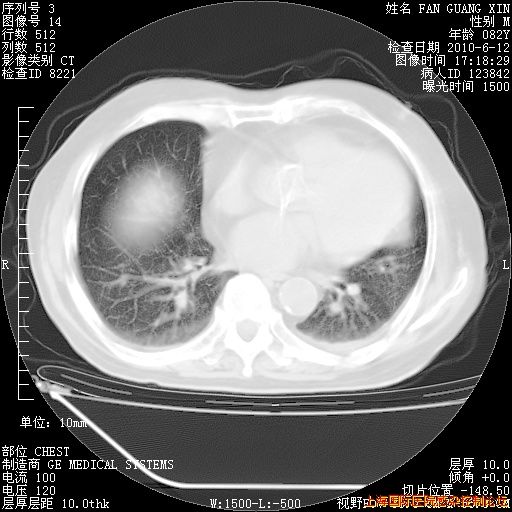

补发6月12日肺部CT肺窗

6月12日肺窗

整整相隔30天的肺部CT好像有所好转啊。甲强龙减量第3天,需要观察体温。